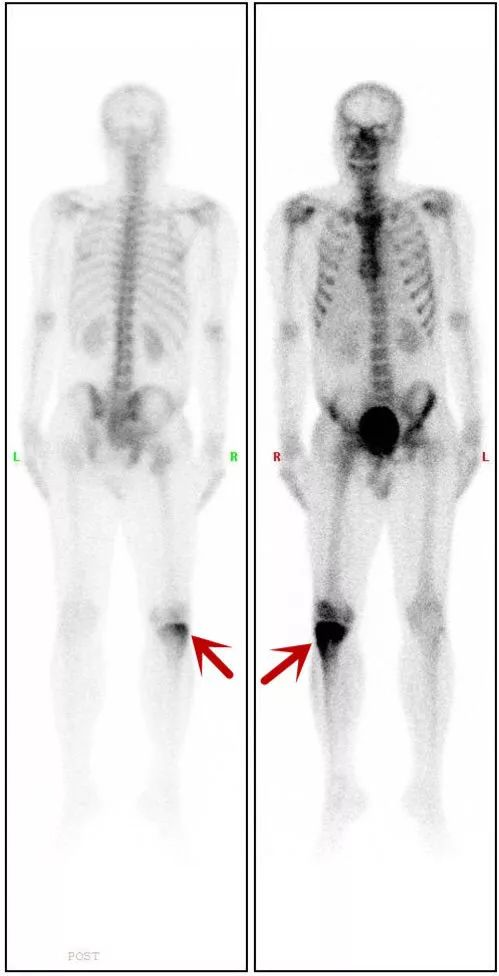

病例三:寻找肿瘤的原发病灶:骨肉瘤

男性,32岁,如图所示:红色箭头标志为可见患者右侧胫骨上段改变,考虑为恶性骨肿瘤。